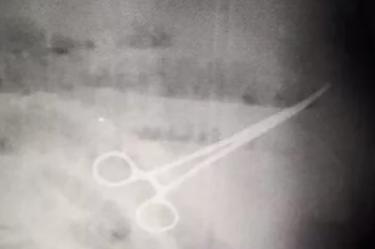

Tras varios días de análisis y estudios, donde se incluyó un lavado de estómago, los médicos realizaron un examen de rayos x donde encontraron las tijeras en el estómago de Iván.

En redes sociales fue difundida una imagen que muestra las tijeras en el estómago de Iván.